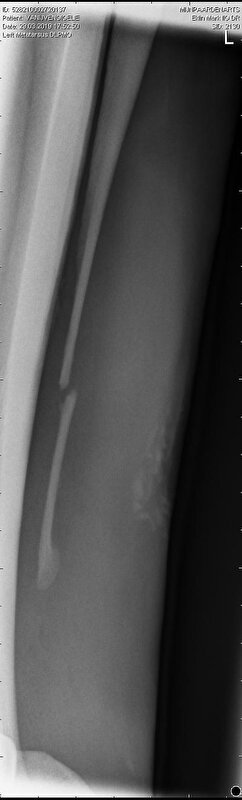

Hierbij de foto's degene die ik naast elkaar gezet heb is links van 5 maart en rechts van 29 maart.

Links dus 5 mrt en rechts 29 mrt

Daar mijn DA nu dus zegt dat het wel aan elkaar kan groeien weer alleen moet je voor boswoekering waken en dat zag ze nu niet. Dat is de reden dat ik nog niet heb geopereerd. Maar ja ik twijfel er zelf een beetje aan maar ben geen dierenarts. Je ziet op de foto's dat het wel al meer naar elkaar toe komt en op rechter foto zie je ook in een hoekje al vaag iets groeien. Dus ja dat zie ik ook en zag op ook een foto van een breuk die verder weg stond maar wel genezen is dus het zal wel kunnen lijkt me.